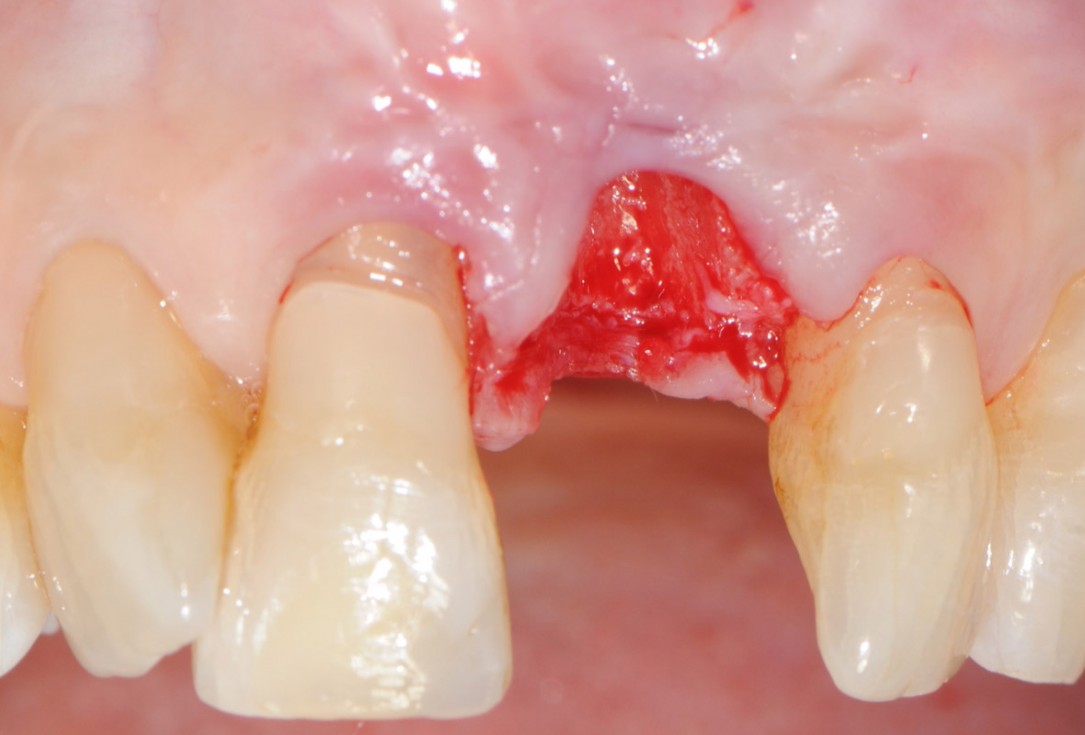

Initial clinical situation with traumatic loss of tooth 21